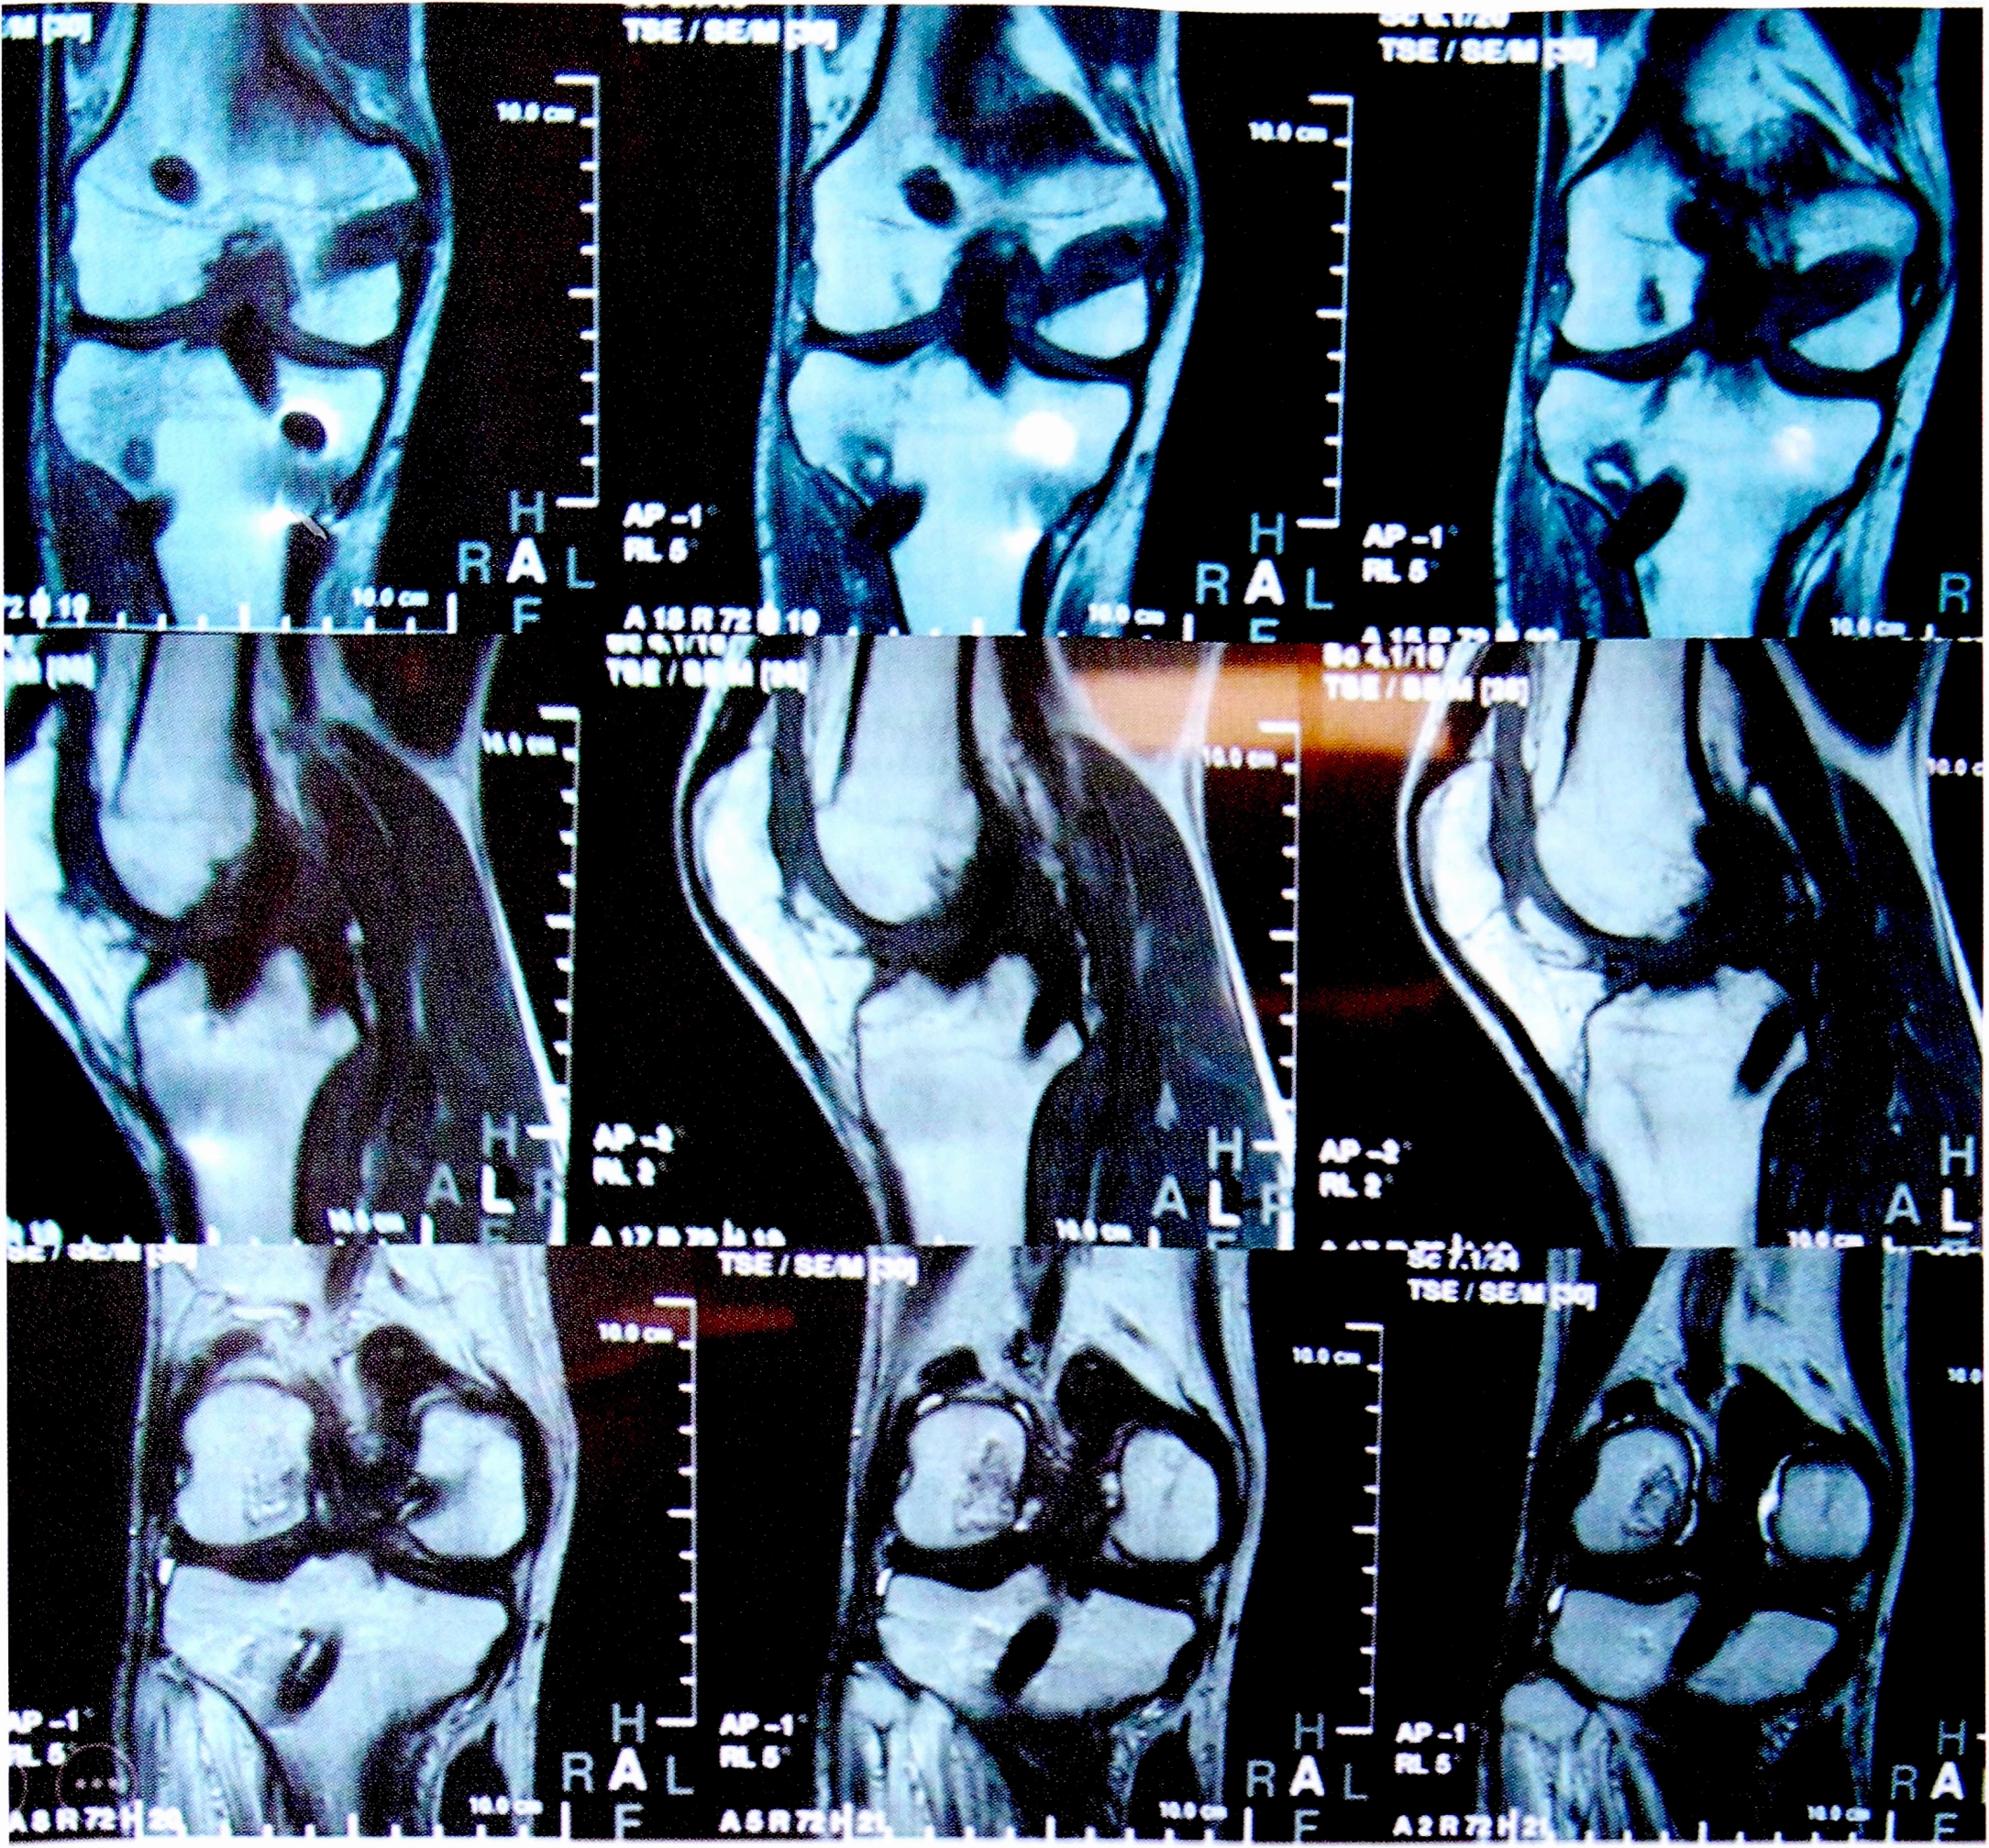

Перед операцией всем пациентам были выполнены МРТ коленного сустава (рис. 1) и рентгенография под нагрузкой (рис. 2). Результаты клинического осмотра, рентгенологических и MPT-исследований фиксировались согласно протоколу IKDC 2000. Для функциональной оценки коленного сустава были использованы опросники IKDC и Lisholm-Gillqist. Болевой синдром оценивался по визуальной аналоговой шкале (VAS).

Рис. 2. Рентгенография коленного сустава с нагрузкой для оценки степени заднего смещения голени.

Fig. 2. Functional X-ray to masure knee posterior instability.